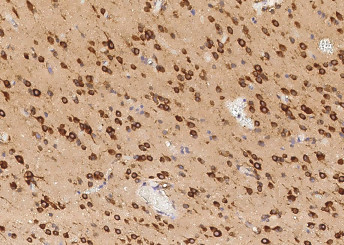

| Application: | IHC (paraffin) |

| Antibody Type: | Monoclonal |

| Clone: | 7B4 |

| Species reactivity: | human |

| Immunogen: | Recombinant Human TLR2 (CD282) Protein |